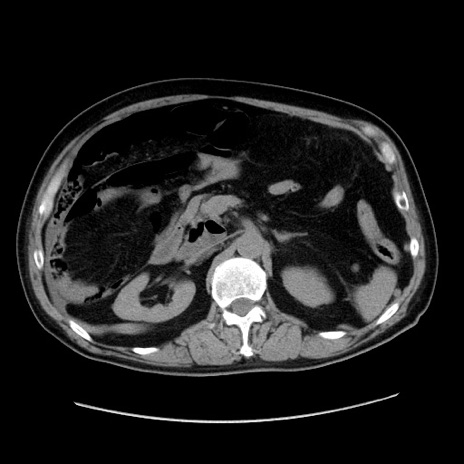

症例30(横断像)

【症例】80歳代男性

【主訴】臍周囲痛

【現病歴】約6時間前から臍下部痛が出現。次第に腹部膨隆・背部痛も生じてきたため来院。背部痛の場所は変化しない。

【身体所見】意識清明、BT 36.3℃、BP  131/87mmHg、P 87bpm、SpO2 100%(RA)、臍周囲自発痛・圧痛あり、反跳痛なし、自発痛部位に一致して板状硬あり、腹部膨隆、腸雑音減弱、CVA tenderness両側陰性。

【データ】WBC 19600、CRP 0.33